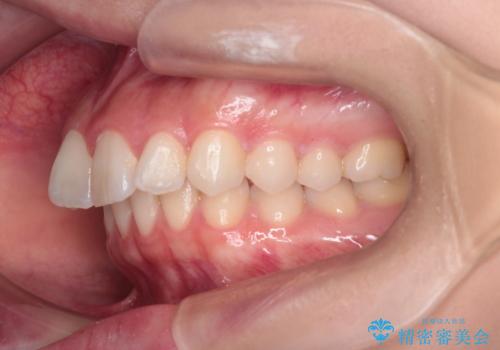

- 患者様は、上下顎の歯列不正と前歯部の突出感を主訴としてご来院されました。診断の結果、上顎左右第一小臼歯を抜歯することでスペースを確保し、歯列全体を整える方針としました。本来はワイヤー矯正が推奨されるケースですが、患者様のご希望により、透明なマウスピース型矯正装置「インビザライン」を使用した治療計画を立案しました。治療期間は約3年で、奥歯の噛み合わせを維持しながら、徐々に前歯の位置を整えました。

インビザラインは見た目の目立ちにくさと取り外しが可能な点がメリットですが、複雑なケースでは治療計画の精密さが求められます。本症例では奥歯の噛み合わせが崩れないよう注意を払いながら、マウスピースの交換タイミングを細かく設定しました。患者様には装着時間を守っていただくことが重要で、1日20時間以上の装着が必須です。また、抜歯部位のスペースを閉じる過程で、歯の動きが停滞しやすい時期もあるため、定期的なチェックを通じて治療が順調に進むよう管理しました。